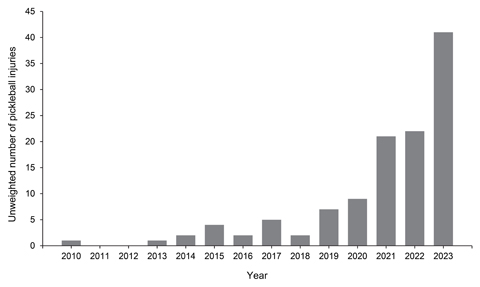

Pickleball-related eye injuries presenting to United States emergency departments, 2010-2023